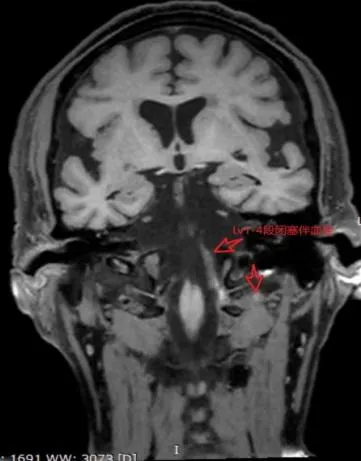

据悉,高分辨磁共振血管壁成像(HRMR-VWI)是近年来发展起来的MRI成像新技术,不仅能评估管腔狭窄程度,还能清晰显示血管壁、动脉粥样硬化斑块及周围结构,分析斑块成分和特征、是否为易损斑块,还能对动脉夹层、血管炎、动脉瘤等疾病进行鉴别诊断,为医生提供更清晰、详细的血管结构图像,也为患者带来了更加个体化、有效的治疗方案。

传统的血管成像方式如MRA、CTA、DSA等主要观察管腔狭窄的情况,不能观察血管壁的具体情况。超声检查可以明确血管内斑块的存在,但对斑块具体成分显示不佳。

高分辨磁共振血管壁成像(HRMR-VWI)技术弥补了传统影像学检查在颅颈部血管疾病的不足,让医生们对管壁精细变化有更直观的了解。该技术具有无创、无辐射、高软组织分辨率、高空间分辨率、高信噪比等优势,已于2019年列入了《中国脑血管病影像指导规范》。